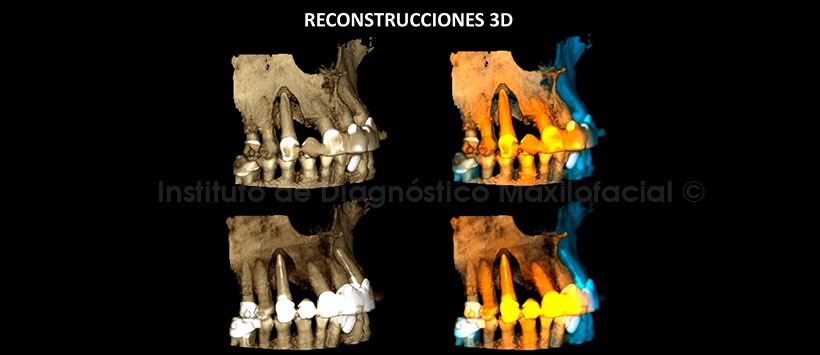

En las reconstrucciones 3D se observan la pérdida de la tabla ósea vestibular y la perdida de soporte óseo periradicular (Figura 6 y 7).